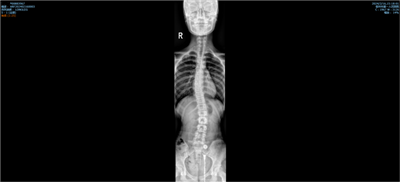

在后续与家属的微信随诊过程中,虽然小尹因为学业原因,没能按照疗程及时就诊,后续治疗也未能持续跟进,这确实有些遗憾,但家属反馈小尹的体态已经有了显著改善。后来复查全脊柱片时发现,其 cobb 角减小至 10.5°,这一结果充分彰显了浮针治疗以及早期治疗介入干预对于脊柱侧弯恢复的重要性。 治疗意义总结纠正青少年脊柱侧弯,其意义远不止于改善体态这么简单。通过矫正体态,能够帮助脊柱恢复正常的对称性,让孩子们在日常的活动中可以保持更好的平衡和姿势,避免因脊柱畸形压迫而导致心肺功能受损,还能减轻背部肌肉和关节所承受的压力,预防或者缓解疼痛症状。同时,体态的改善对于青少年的心理健康也有着积极影响,能够增强他们的自信心,让他们更加积极乐观地面对生活和学习。